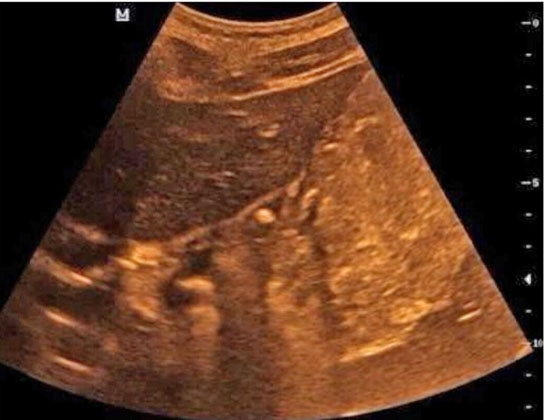

就在这时,有朋友给小英的妈妈推荐了胃肠超声检查。按照约定的时间,小英一大早就空腹来到齐鲁医院青岛院区健康管理中心,喝下了医生为她特制的“黑芝麻糊”后,B超室医生为她进行了胃肠超声检查,结果发现小英胃的贲门口位置有一个大约5mm的溃疡,与她疼痛的位置相符。

胃肠超声,又叫胃十二指肠口服超声造影,是胃肠道疾病的影像学检查方法之一。健康管理中心副主任张萍介绍说,之前超声不能看胃,因为胃是空腔脏器,里面有气体,而超声比较怕气体。但是如果有什么办法可以将胃里的空气赶走,让它变得像实质脏器,问题不就解决了吗?于是胃窗造影剂应运而生。

“胃肠超声就是通过口服纯粮食造影剂,在超声下能够看到粘膜层及胃壁各层结构,筛查疾病,发现可疑病变,并观察病变的范围及侵犯程度。”她说。